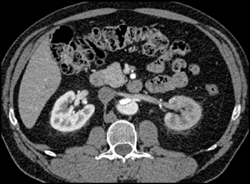

Diagnosis

Diseased Coronary Arteries